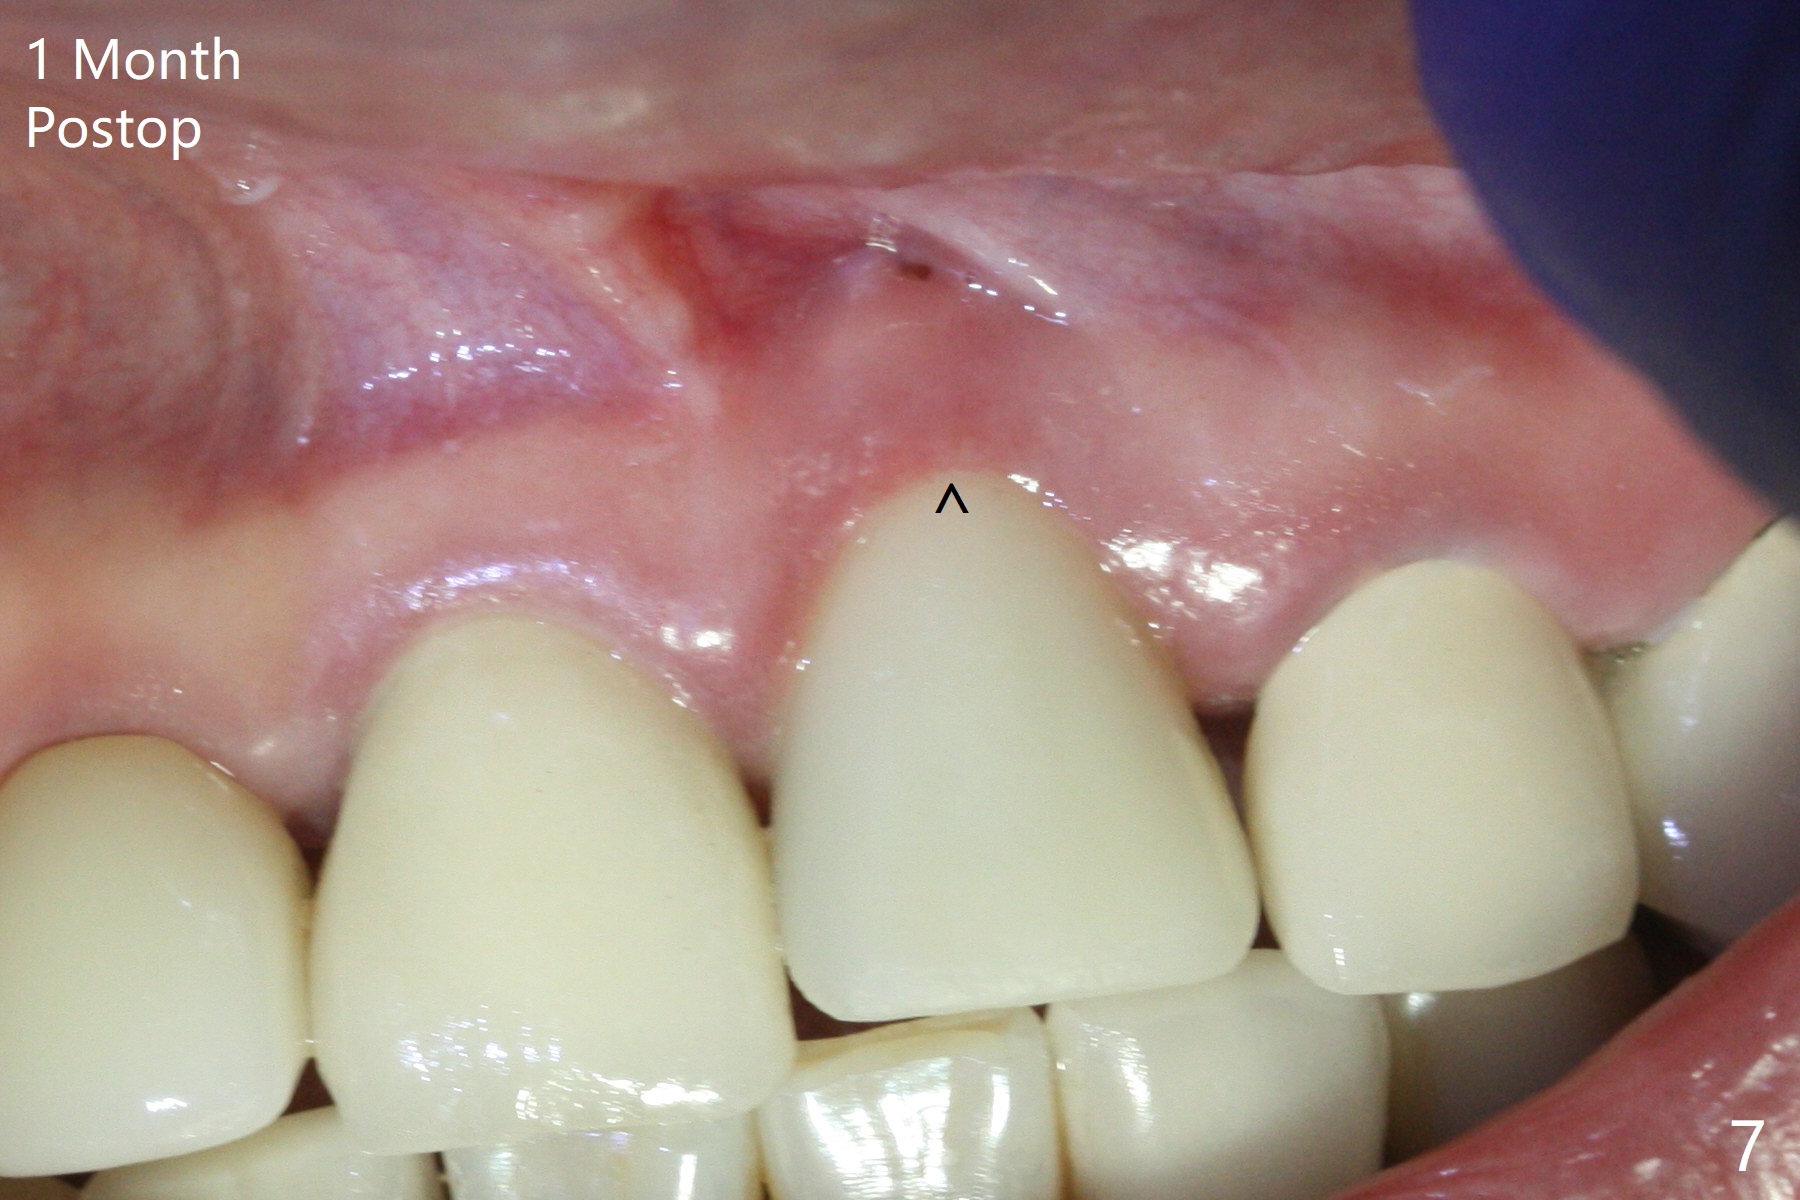

Nasal Floor

The buccal contour at #9 seems to be slightly concave preop (Fig.1,2 (*)). In fact the buccal plate is found to be lost when the tooth is extracted. Osteotomy is initiated as palatal as possible apical, but the occlusion dictates the coronal end of the osteotomy should be buccal, leaving the buccal gap ~ 2 mm for bone graft. The initial osteotomy (18 mm deep) appears to be close to the Incisive Foramen (Fig.3 blue dashed line). The nasal floor appears to be intact when the drill is removed. Subsequent osteotomy is adjusted so that the apical end of the osteotomy moves distal; when a 3.8x15 mm dummy implant is partially placed, there is clearance (Fig.4). It remains so when a definitive implant is seated (Fig.5); Vanilla graft is placed (Fig.5 *) before placement of a 4.5x5.5(3) mm abutment. More allograft is placed when an immediate provisional is fabricated (Fig.6 arrow and *). The gingiva remains to be recessive 1 month postop (Fig.7). It seems to be related to the bulky gingival margin of the provisional (Fig.8 *). After trimming the latter (Fig.9 *), the gingival margin immediately returns close to normal (Fig.10). The gingival margin is even between #8 and 9 two months postop, but the bone graft is exposed apically (Fig.11 ^). It may heals by itself. Otherwise debridement, regraft, PRF and suture are pending. The coronal portion of the socket heals 4 months postop (Fig.12). The gingival cuff forms by the immediate provisional (which is removed for impression) 4 months postop (Fig.13 *). While the full Zirconia crown at #7 remains intact (Fig.14), the PFM at #9 has porcelain chip (Fig.15). It is partially due to the occlusion; while the crown at #7 has clearance with the opposing dentition (Fig.16 *), the one at #9 has no. The access hole at #9 (Fig.17 *) seems to weaken the crown structure. There is no access hole at #7. No solid posterior support is another contributing factor for chip (Fig.18). The buccal plate has mild atrophy at #7 and 9 (Fig.19 *). A piece of bone graft is being expelled apically at #9 (Fig.20 >) and is removed subsequently (Fig.21). Before impression for repacking porcelain, the opposing incisal edge has been shortened (Fig.22 arrows, as compared to Fig.16). Since the ideal access hole is at the incisal edge (Fig.25 black circle), buccal to the existing one (Fig.24 A), the abutment is torqued before the repaired crown is recemented (Fig.23). Finally the crown has occlusal clearance (Fig.26). Porcelain chips again around the access hole of PFM 1.5 years post 2nd cementation. The dense bone at the crest (*) cannot explain why the abutment is not loose, since it remains incompletely seated (>). As it was trimmed short, an angled abutment is used (Fig.28). The coronal end is lingual, while #9/24 is edge to edge. The lingual aspect of the coronal end of the abutment is heavily trimmed to reduce bulkiness. To prevent chip, Zirconium crown will be fabricated in spite of the fact that it does not match the PFM of #8 (potential shade discrepancy). The patient is pleased with the new Zirconia crown (Fig.29).